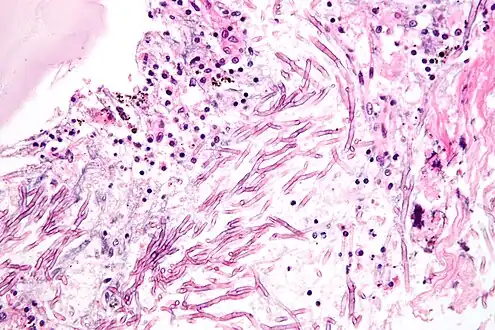

A. fumigatus (the most common species) infections are primary pulmonary infections and can potentially become a rapidly necrotizing pneumonia with a potential to disseminate. The organism can be differentiated from other common mold infections based on the fact that it takes on a mold form both in the environment and in the host (unlike Candida albicans which is a dimorphic mold in the environment and a yeast in the body).

Aspergillosis

Aspergillosis is the group of diseases caused by Aspergillus. The most common species among paranasal sinus infections associated with aspergillosis is A. fumigatus.[28] The symptoms include fever, cough, chest pain, or breathlessness, which also occur in many other illnesses, so diagnosis can be difficult. Usually, only patients with already weakened immune systems or who suffer other lung conditions are susceptible.

In humans, the major forms of disease are:[29][30]

- Acute invasive aspergillosis, a form that grows into surrounding tissue, more common in those with weakened immune systems such as AIDS or chemotherapy patients

- Allergic bronchopulmonary aspergillosis, which affects patients with respiratory diseases such as asthma, cystic fibrosis, and sinusitis

- Aspergilloma, a "fungus ball" that can form within cavities such as the lung

- Disseminated invasive aspergillosis, an infection spread widely through the body